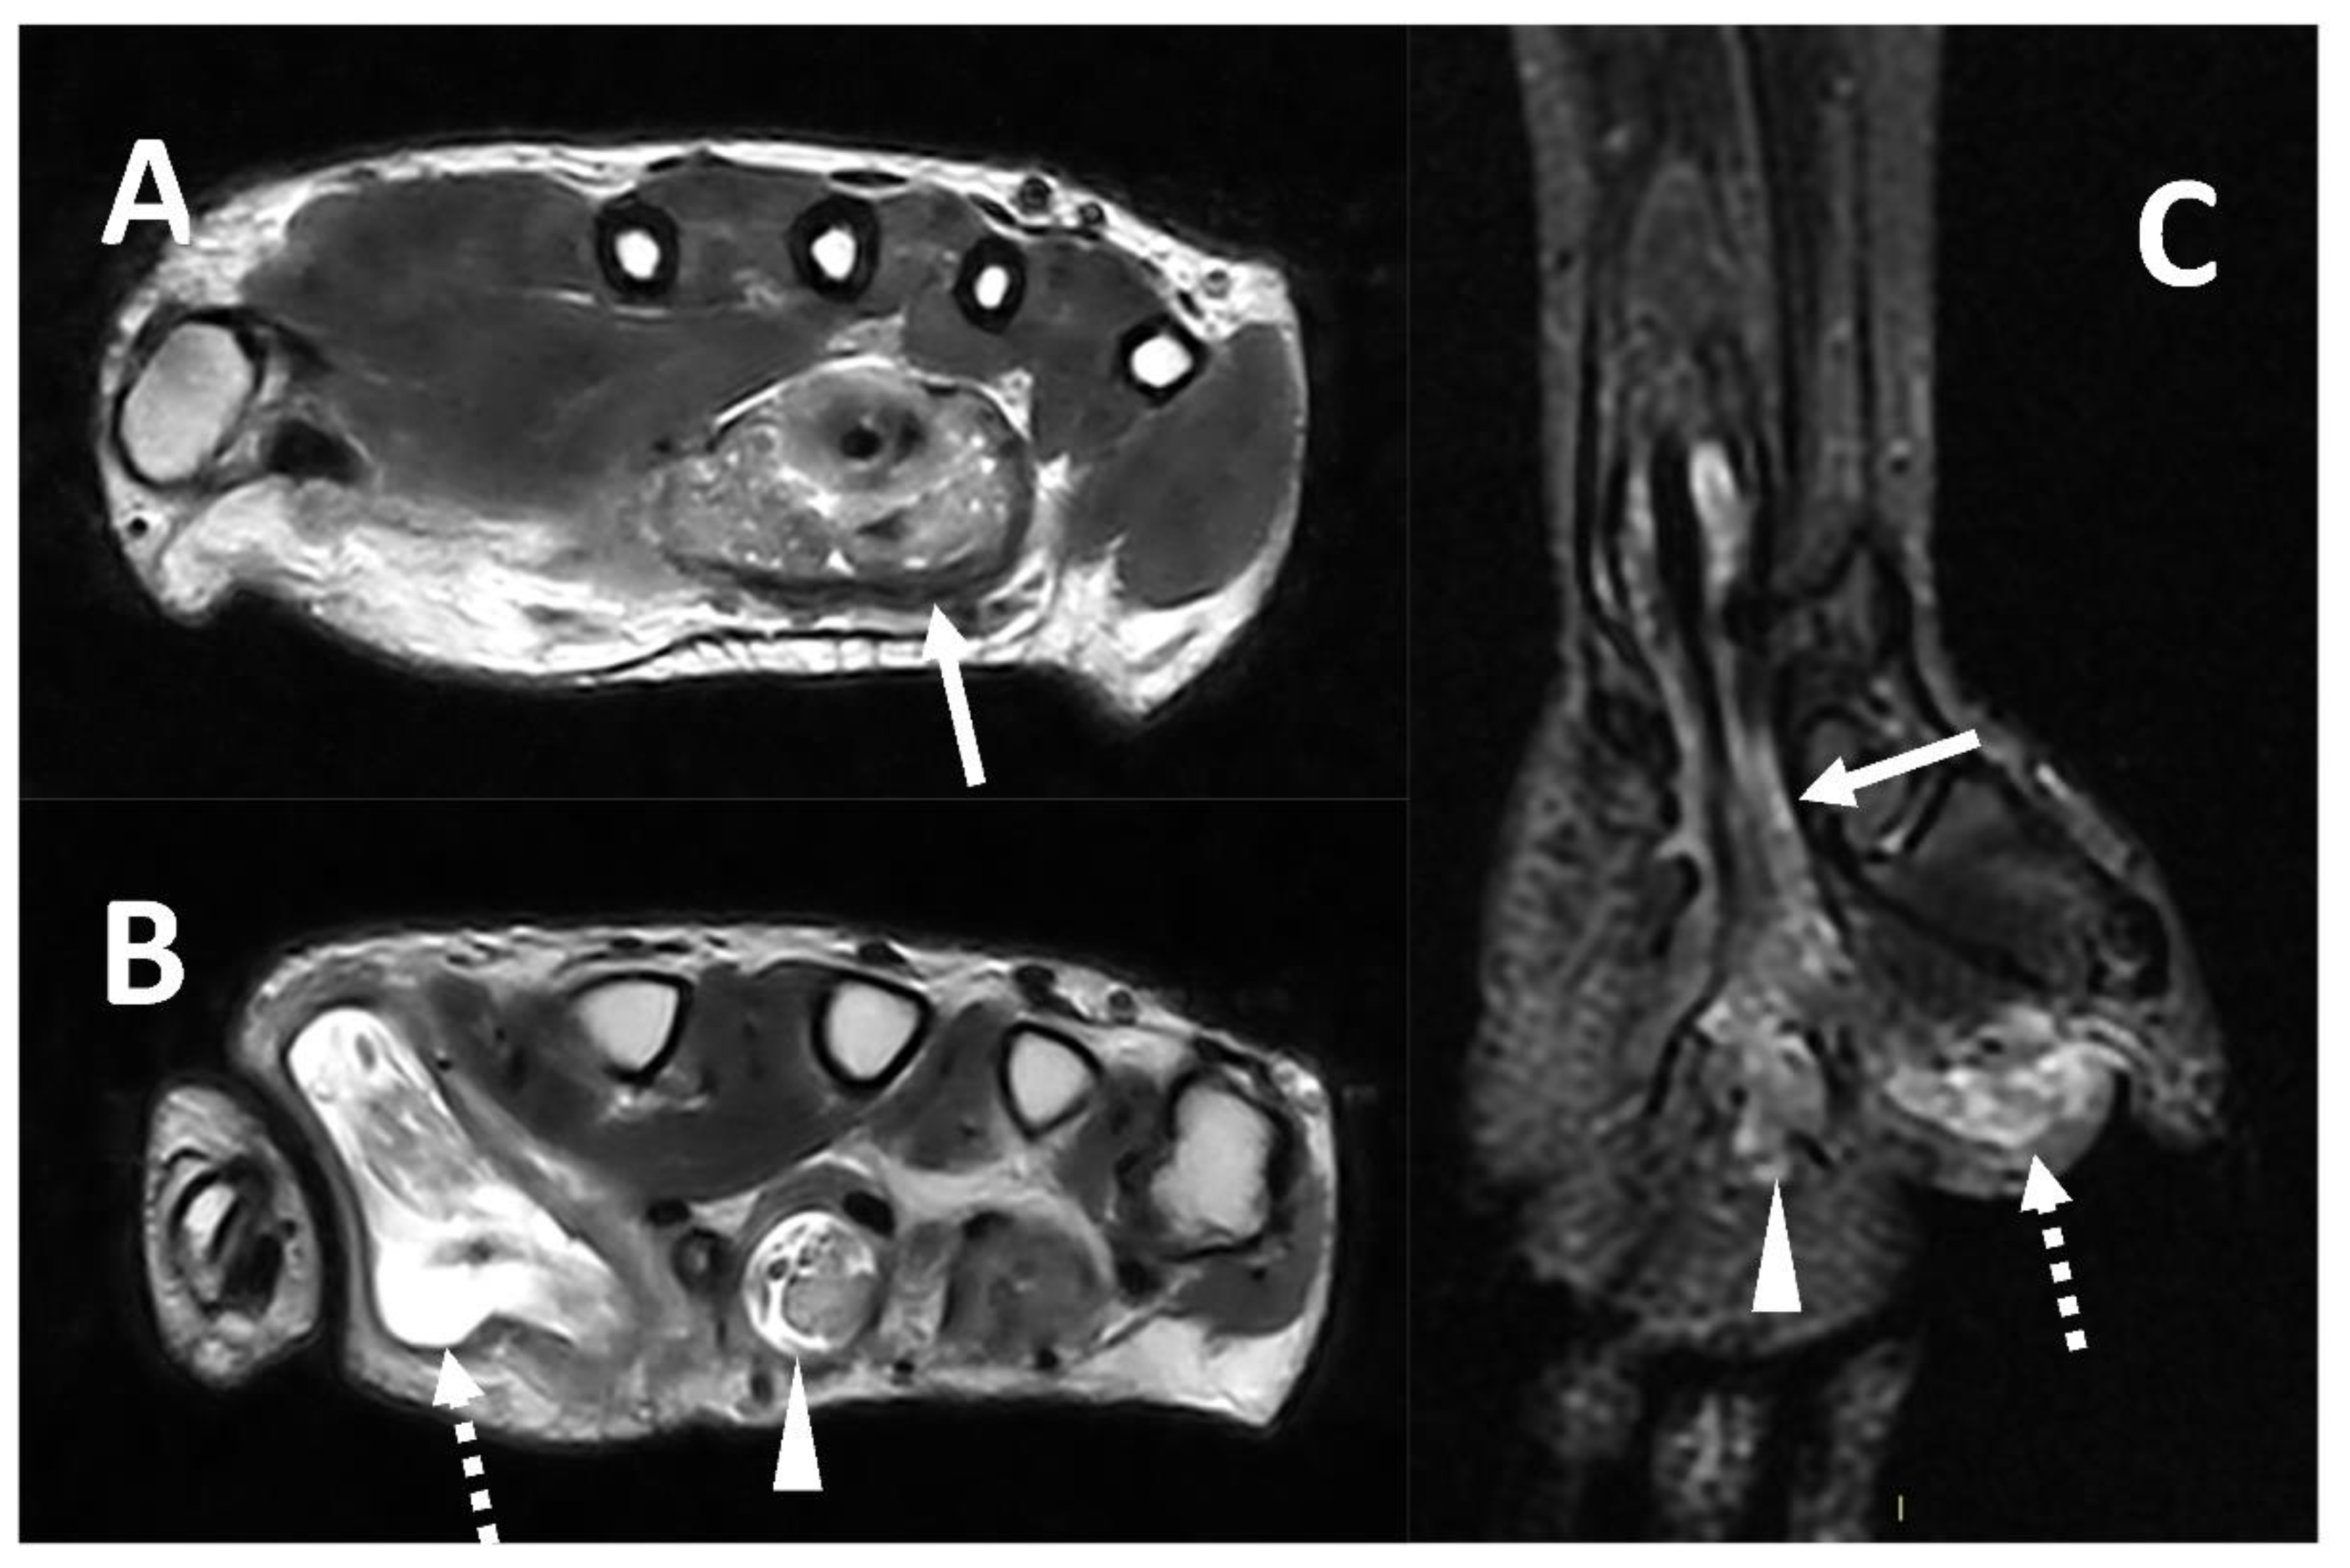

2.4. Abscess

- Fayad, L.M.; Carrino, J.A.; Fishman, E.K. Musculoskeletal infection: Role Of CT In the emergency department. Radiographics 2007, 27, 1723–1736. [Google Scholar] [CrossRef] [PubMed]

- Ma, L.D.; Frassica, F.J.; Bluemke, D.A.; Fishman, E.K. CT and MRI evaluation of musculoskeletal infection. Crit. Rev. Diagn. Imaging 1997, 38, 535–568. [Google Scholar]

- Chandnani, V.P.; Beltran, J.; Morris, C.S.; Khalil, S.N.; Mueller, C.F.; Burk, J.M.; Bennett, W.F.; Shaffer, P.B.; Vasila, M.S.; Reese, J. Acute experimental osteomyelitis and abscesses: Detection with MR IMAGING versus CT. Radiology 1990, 174, 233–236. [Google Scholar] [CrossRef] [PubMed]

- McGuinness, B.; Wilson, N.; Doyle, A.J. The “penumbra sign” on t1-weighted MRI for differentiating musculoskeletal infection from tumour. Skelet. Radiol. 2007, 36, 417–421. [Google Scholar] [CrossRef]

- Chun, C.W.; Jung, J.-Y.; Baik, J.S.; Jee, W.-H.; Kim, S.K.; Shin, S.H. Detection of soft-tissue abscess: Comparison of diffusion-weighted imaging to contrast-enhanced MRI. J. Magn. Reason. Imaging 2018, 47, 60–68. [Google Scholar] [CrossRef]

- Harish, S.; Chiavaras, M.M.; Kotnis, N.; Rebello, R. MR imaging of skeletal soft tissue infection: Utility of diffusion-weighted imaging in detecting abscess formation. Skelet. Radiol. 2011, 40, 285–294. [Google Scholar] [CrossRef]